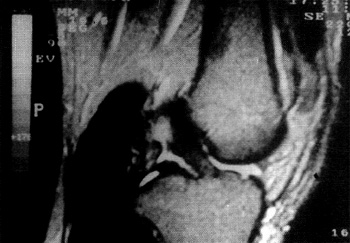

Fig. 2: Lesión Tipo I intrasubstancia, secuencia Tl.

TIPO 1 0 LEVES: Lesión intra-sustancia ubicada en el tercio medio o distal, raras veces ocupa los dos tercios distales. El LCA presenta sus bordes bien definidos, esta tenso y con incremento franco de señal en el sector central tanto en T2 como en las imágenes de densidad protonica; en T1 puede mostrarse levemente hiperintenso. Interpretamos que si bien prevalece el componente edematoso, el leve aumento de señal en T1 indica la presencia de hemoglobina en forma de metahemoglobina.

Fig. 3: Lesión Tipo I intrasubstancia, secuencia D.P.